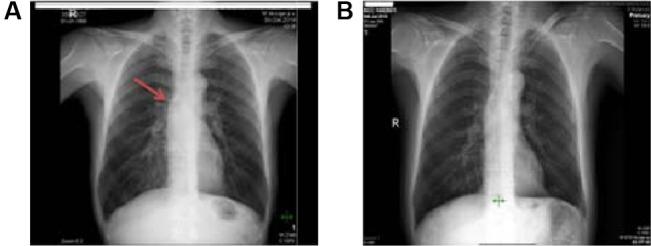

A 55-year-old man presented with oral mucosal ulcers, blackening of both hands, and hyperpigmentation on axillary, anal, and inguinal regions for the last 3 months, which were all progressive. The patient was referred to the oncology department with the diagnosis of acanthosis nigricans for investigation of an underlying malignancy. He was a smoker. A computed tomography scan of thorax revealed enlarged mediastinal lymphadenopathies and a lesion on the left upper lobe. Fine-needle aspiration biopsy of the mediastinal lesion was consistent with squamous cell carcinoma, and biopsies of the skin and oral mucosal lesion also further confirmed the diagnosis of acanthosis nigricans. After docetaxel and cisplatin chemotherapy, a significant improvement in his skin and mucosal lesions was observed with almost complete resolution of the pulmonary lesion and the mediastinal lymph nodes.

一名55岁男性在过去3个月出现口腔黏膜溃疡、双手变黑以及腋窝、肛门和腹股沟区域色素沉着,且均呈进行性发展。该患者因黑棘皮病被转诊至肿瘤科,以排查潜在恶性肿瘤。他有吸烟史。胸部计算机断层扫描显示纵隔淋巴结肿大及左上叶有一病灶。纵隔病灶的细针穿刺活检结果符合鳞状细胞癌,皮肤及口腔黏膜病灶的活检也进一步证实了黑棘皮病的诊断。多西他赛和顺铂化疗后,其皮肤和黏膜病灶有显著改善,肺部病灶及纵隔淋巴结几乎完全消退。